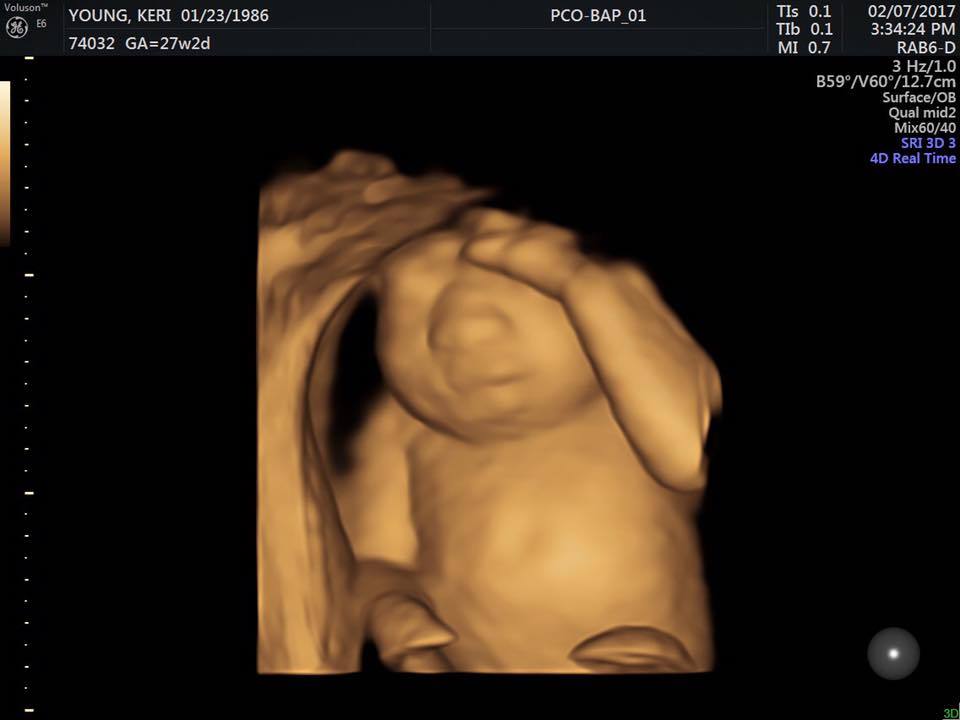

Keri Young era in al noualea cer fiindca a aflat ca urmeaza sa devina mamica, insa fericirea ei a fost umbrita de o veste cumplita. Medicii i-au spus ca bebelusul ei nu are creier.

Keri Young si sotul ei, Royce, isi doreau foarte mult sa devina parinti. Cei doi tineri din Oklahoma City au reusit sa conceapa un bebelus, insa medicii le-au dat o veste cumplita: copilul din burta nu are creier.